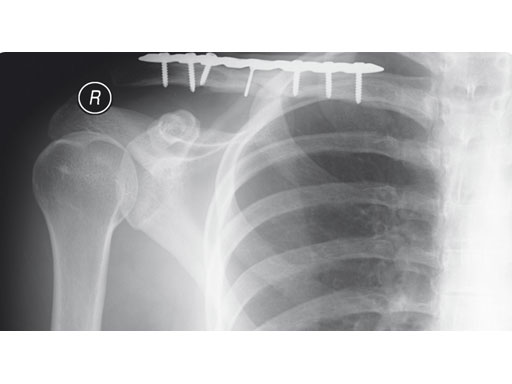

A 22-year-old man sustained an open clavicle fracture after a motorcycle injury.

Fig 1ab Preoperative x-rays.

Fig 2ab Postoperative images.

Fig 3ab X-rays taken 3 months postoperatively.

Case provided by Harry A Hoyen III, Cleveland, USA